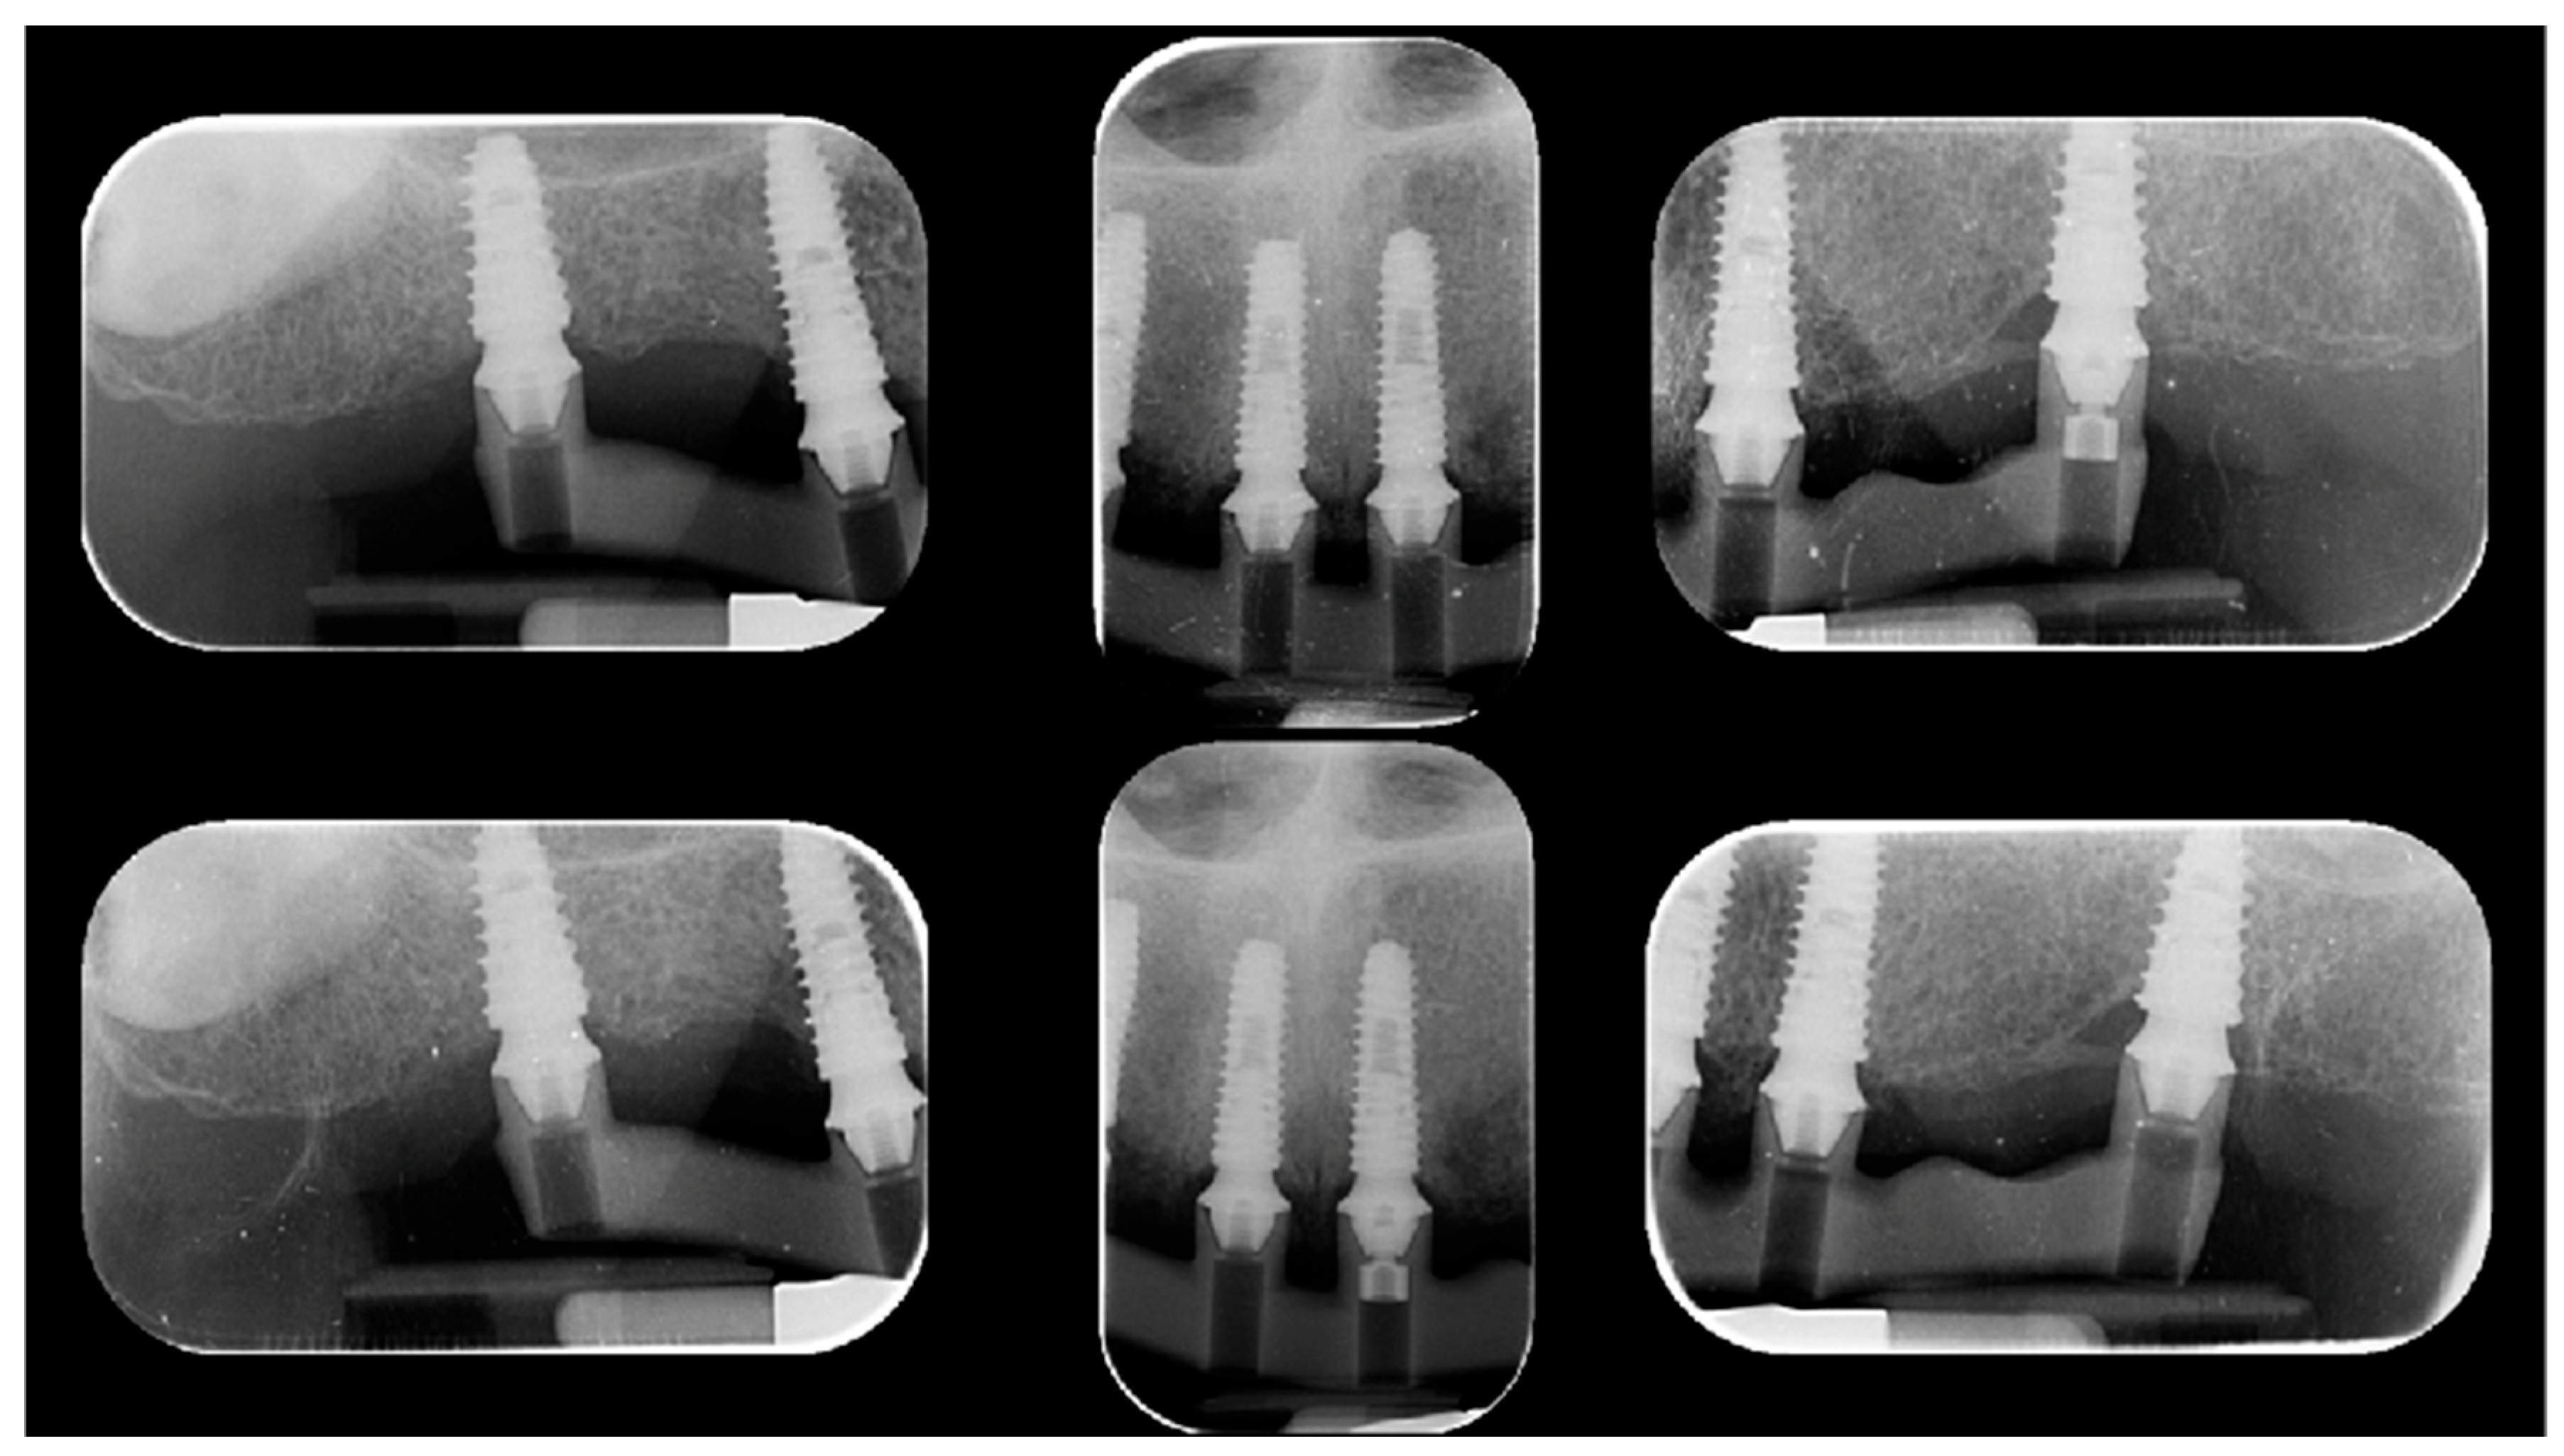

Passive fit of the metal verification bar was assessed using the one-screw test (Sheffield test) combined with tactile verification using a dental explorer. The Sheffield test consisted of tightening a single prosthetic screw to 5 Ncm at one terminal implant or at the most anterior implant, while leaving all other screws unfastened (Figure 3). Standardized periapical radiographs were obtained using a Rinn holder.

Passive fit was assumed when the framework seated completely without visible gaps, rocking, or distortion at the remaining implant interfaces. Conversely, lifting or marginal discrepancies detected clinically or radiographically were interpreted as evidence of misfit [13,14].

Similarly, the one-screw (Sheffield) test showed complete passive seating of the verification framework in all patients, with no detectable gaps, rocking, or distortion, corresponding to a 100% positive outcome.

Figure 3. Periodical radiographs according to the Sheffield test (on screw test).